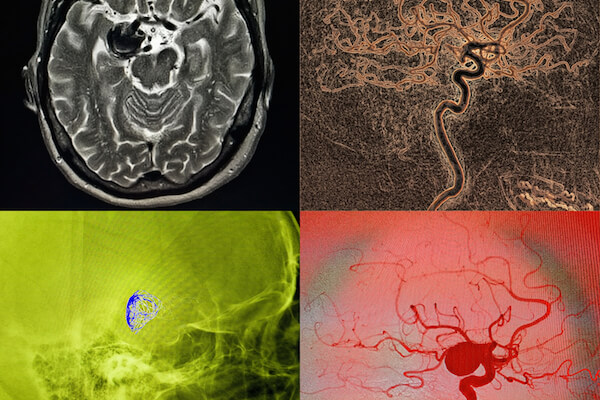

This is the branch of radiology that deals with the endovascular treatment of intracranial diseases.

These procedures are mainly defined as follows:

- embolization of cerebral aneurysms through coiling technique or flow diverter implant

- embolization of AVMs (arteriovenous malformations), AVFs (arteriovenous fistulas) or dAVFs (dural arteriovenous fistulas, or fistulas localized in the dura layers)

- intracranial stenting (both for the treatment of brain stenosis and for assistance in the embolization of aneurysms)

- Desobstruction of cerebral arteries in patients with ischemic stroke